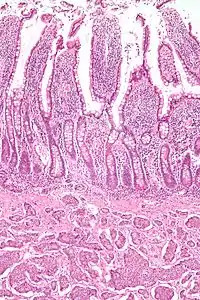

NETs are often small, yellow or tan masses, often located in the submucosa or more deeply intramurally, and they can be very firm due to an accompanying intense desmoplastic reaction. The overlying mucosa may be either intact or ulcerated. Some GEP-NETs invade deeply to involve the mesentery.[72] Histologically, NETs are an example of "small blue cell tumors," showing uniform cells which have a round to oval stippled nucleus and scant, pink granular cytoplasm. The cells may align variously in islands, glands or sheets. High power examination shows bland cytopathology. Electron microscopy can identify secretory granules. There is usually minimal pleomorphism but less commonly there can be anaplasia, mitotic activity, and necrosis.

NETs from a particular anatomical origin often show similar behavior as a group, such as the foregut (which conceptually includes pancreas, and even thymus, airway and lung NETs), midgut and hindgut; individual tumors within these sites can differ from these group benchmarks:

- Midgut NETs are argentaffin positive, can produce high levels of serotonin 5-hydroxytryptamine (5-HT), kinins, prostaglandins, substance P (SP), and other vasoactive peptides, and sometimes produce corticotropic hormone (previously adrenocorticotropic hormone [ACTH]). Bone metastasis is uncommon.